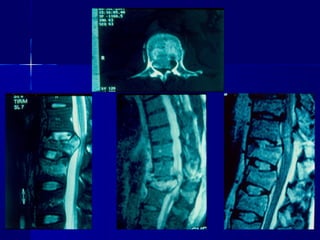

MRI

TTyyppee AA

((BBuurrsstt ffrraaccttuurree))

AA 33..22

MRI TTyyppee AA ((BBuurrsstt ffrraaccttuurree)) AA 33..22